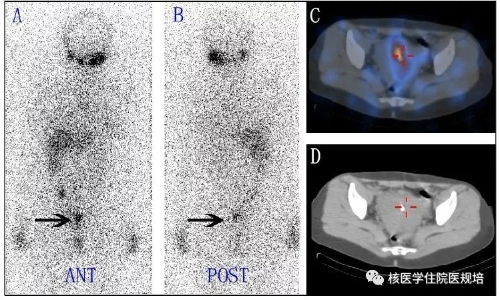

Rx-WBS可出现假阴性或假阳性显像结果。假阴性显像结果主要原因考虑为病灶在平面显像时的重叠干扰。Rx-WBS假阳性显像一般有以下几种成因:1.钠碘转运体(NIS)的表达2. 131I标记的甲状腺激素的代谢3.放射性131I在体液的滞留4.在炎症组织中滞留和吸收5.生理性分泌物的污染等。Rx-WBS假阳性显像全身均可能出现,包括头颈部、胸腹部、盆部、四肢等部位。其中,盆腔假阳性女性患者多见。DTC肿瘤转移到盆腔的概率很低,但当患者全身显像出现盆腔异常131I摄取时,往往可提示其他的临床信息,如子宫(子宫肌瘤、子宫内膜腺肌病、子宫内膜增厚、宫内绝育器、宫颈慢性炎症等)、卵巢(卵巢巧克力囊肿、卵巢甲状腺囊肿、卵巢腺瘤等)、膀胱、肠道、输卵管结扎等病生理情况(图4、图5、图6)。

图6 双侧输卵管结扎致异常131I摄取